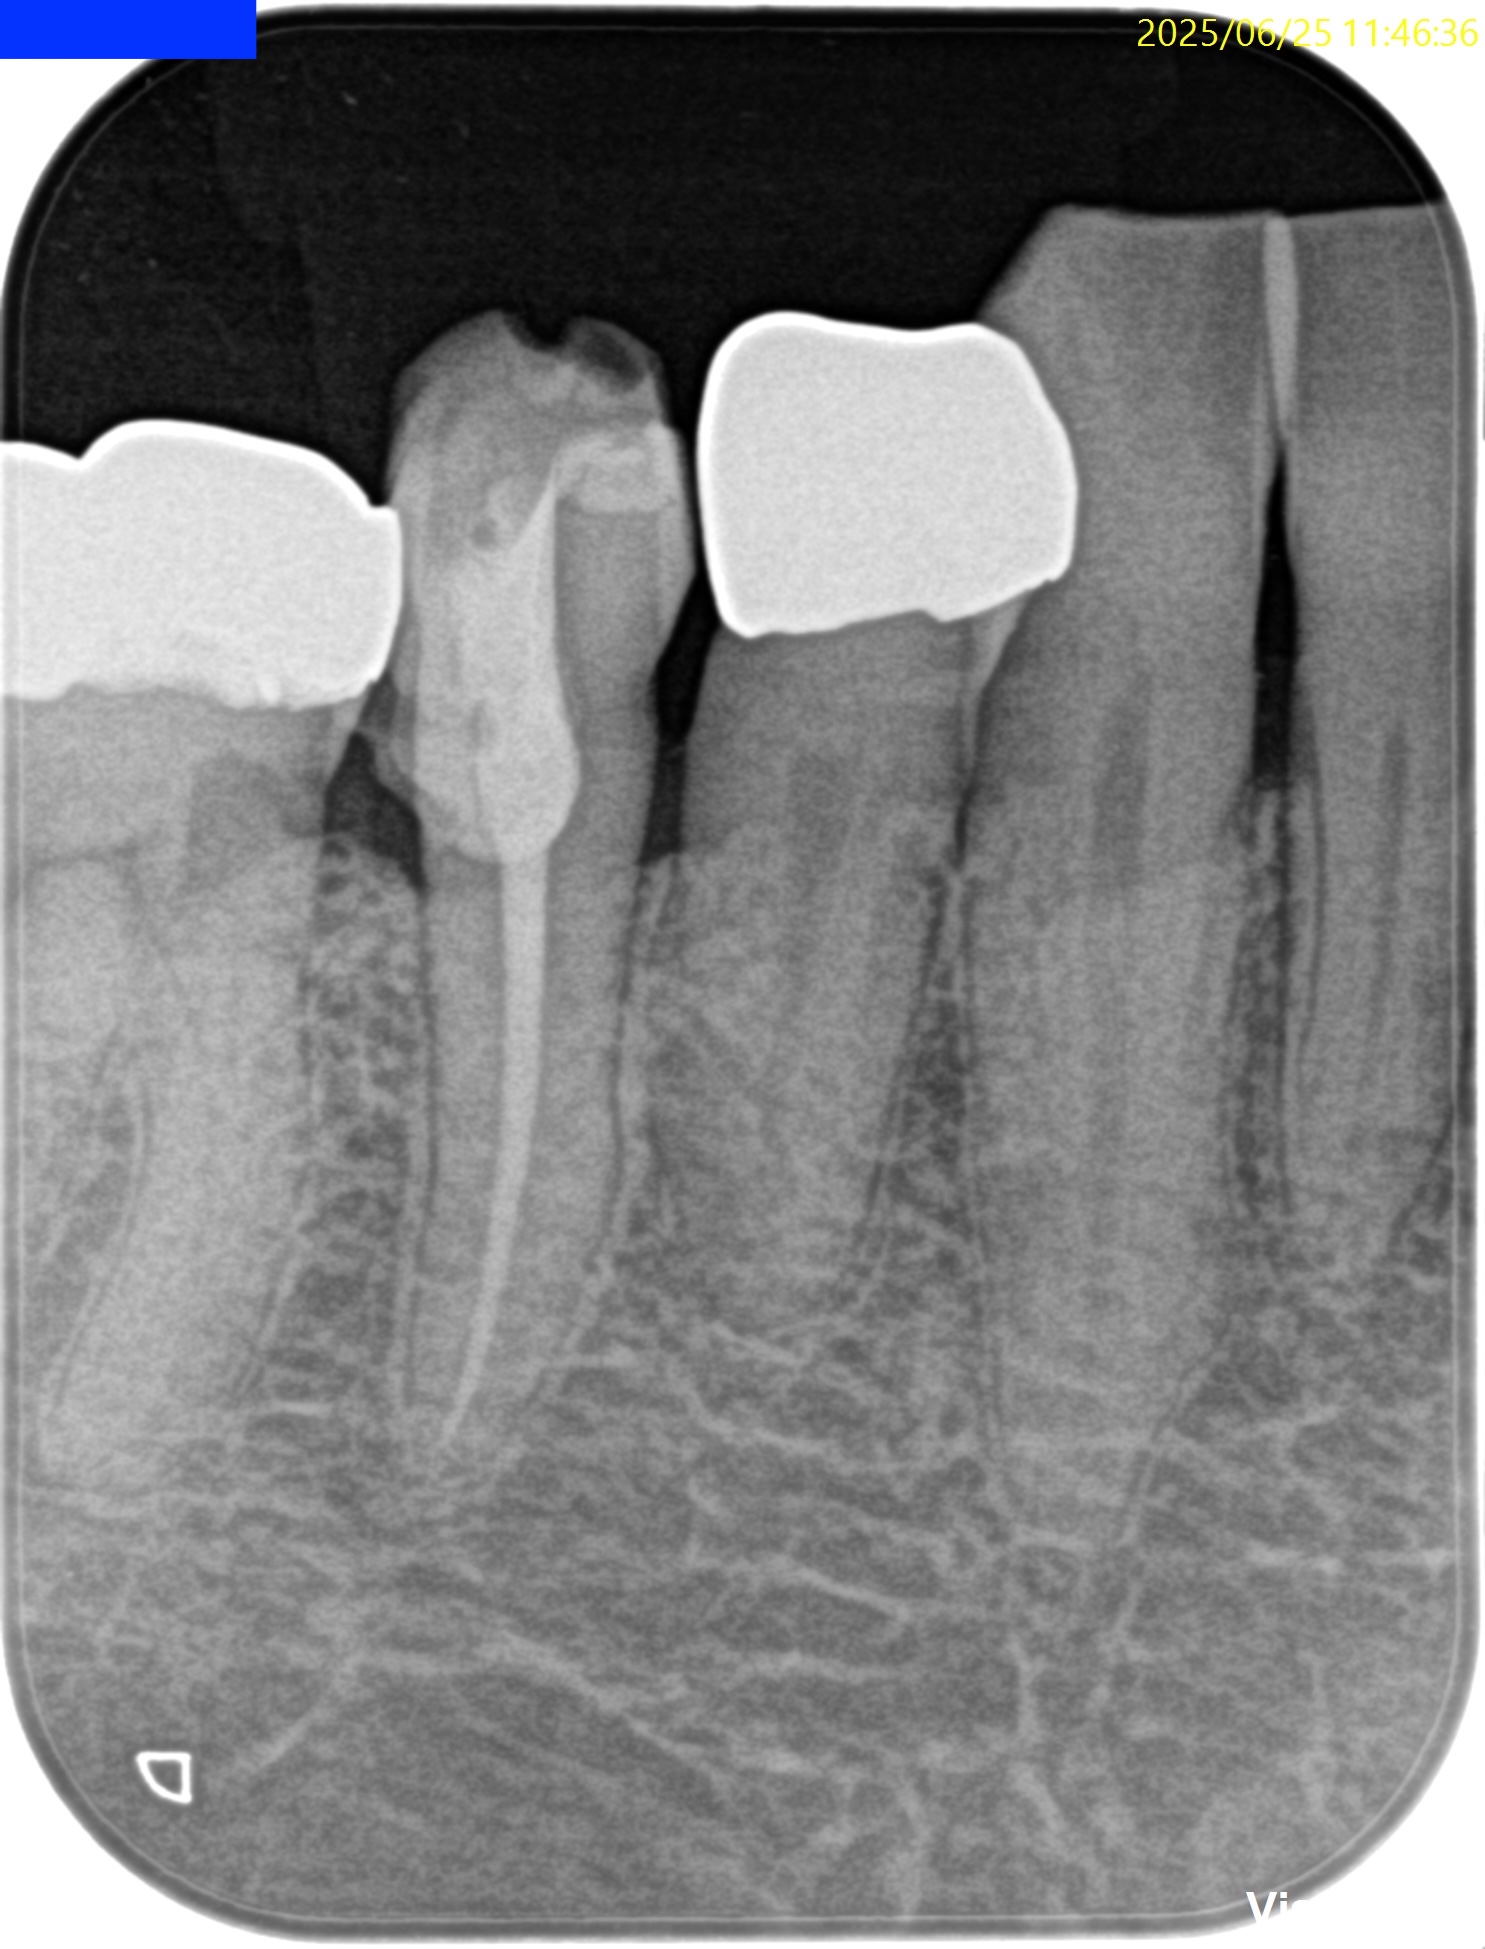

PA(2025.6.25)

検査でなく、PAで初めて患歯が#29だとわかる。

歯髄に迫る大きな虫歯が保険の修復物の下部にある。

CBCT(2025.6.25)

が、根尖病変はない。